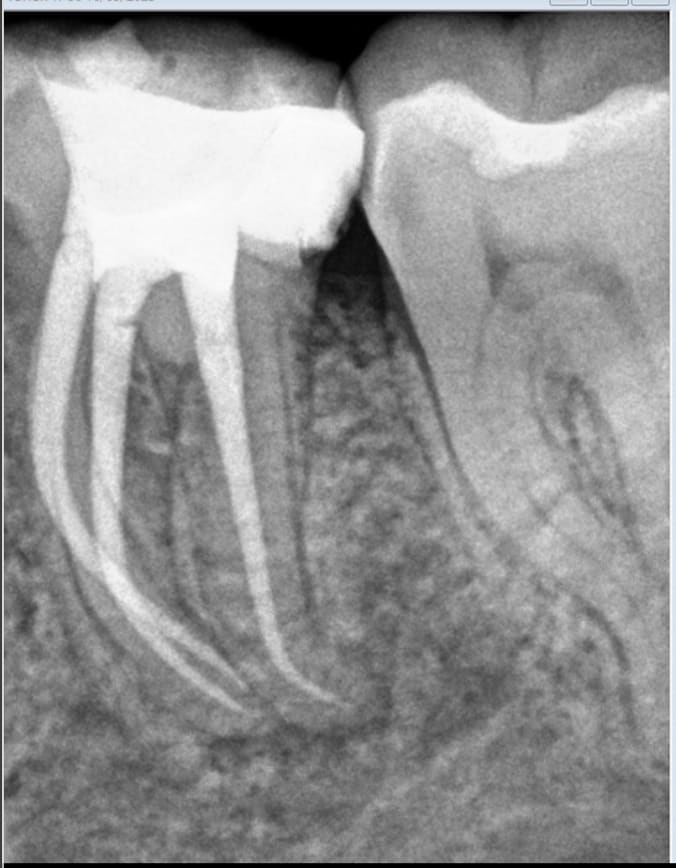

regardes le justicier inquiet , toi qui aimes voir les radios , je viens de faire une endo cet aprem .

et je t ai même pris la radio avant , chose que je ne fais pas souvent ( puisqu elles ne me servent à rien tellement elles sont pourries mes radios ) , je l ai faite rien que pour toi , pour ne pas que tu crois que je te sorte encore une " endo de ma vie " comme tu as su me le dire la dernière fois , la radio d' avant étant datée d aujourd'hui .

bon le canal est très fin , tordu et profond , et tu crois que ça m inquiète quand au choix de la pétale ou de je ne sais quoi ? :-))

m en fout complètement , je tape dans ce que j ai sous la main . du moment que ça a une bonne gueule et que c est tranchant y a pas de tress .